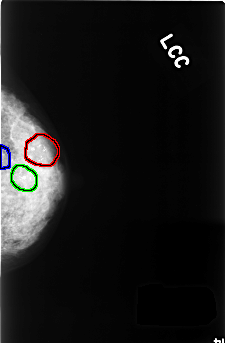

FILE: C_0375_1.LEFT_CC.OVERLAY

TOTAL_ABNORMALITIES 3

ABNORMALITY 1

LESION_TYPE CALCIFICATION TYPE PLEOMORPHIC DISTRIBUTION CLUSTERED

ASSESSMENT 4

SUBTLETY 5

PATHOLOGY BENIGN

TOTAL_OUTLINES 1

BOUNDARY

ABNORMALITY 2

ABNORMALITY 3